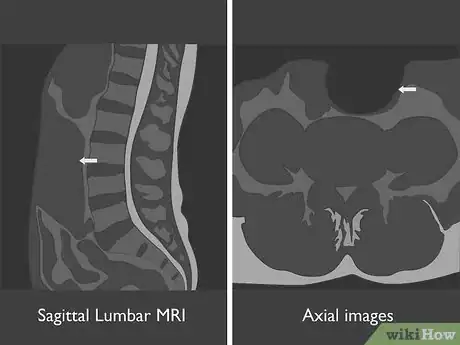

2Identify the type of MRI used in each image. At a minimum, you'll have a sagittal lumbar MRI, which is a vertical image that looks at your spine from the side. You may also have axial images, which look at a cross-section of an individual disc. Think of these as similar to slicing a tree log in sections to look at the rings on the tree. Each of these uses one of two imaging techniques:[3]

- T1-weighted images show greater contrast between tissues, which allows your doctor to more accurately diagnose disc herniation. T1-weighted images are used for sagittal MRIs but not typically for axial MRIs.

- T2-weighted images brighten the cerebrospinal fluid of your spinal canal, making it easier for your doctor to see different types of infection that might be missed by a T1-weighted image. T2-weighted images are used for both sagittal and axial MRIs.

Tip: If you see a bright, white line running down your spine on a sagittal MRI, you're looking at a T2-weighted image. The white line is the cerebrospinal fluid of your spinal canal, which holds your nerves.